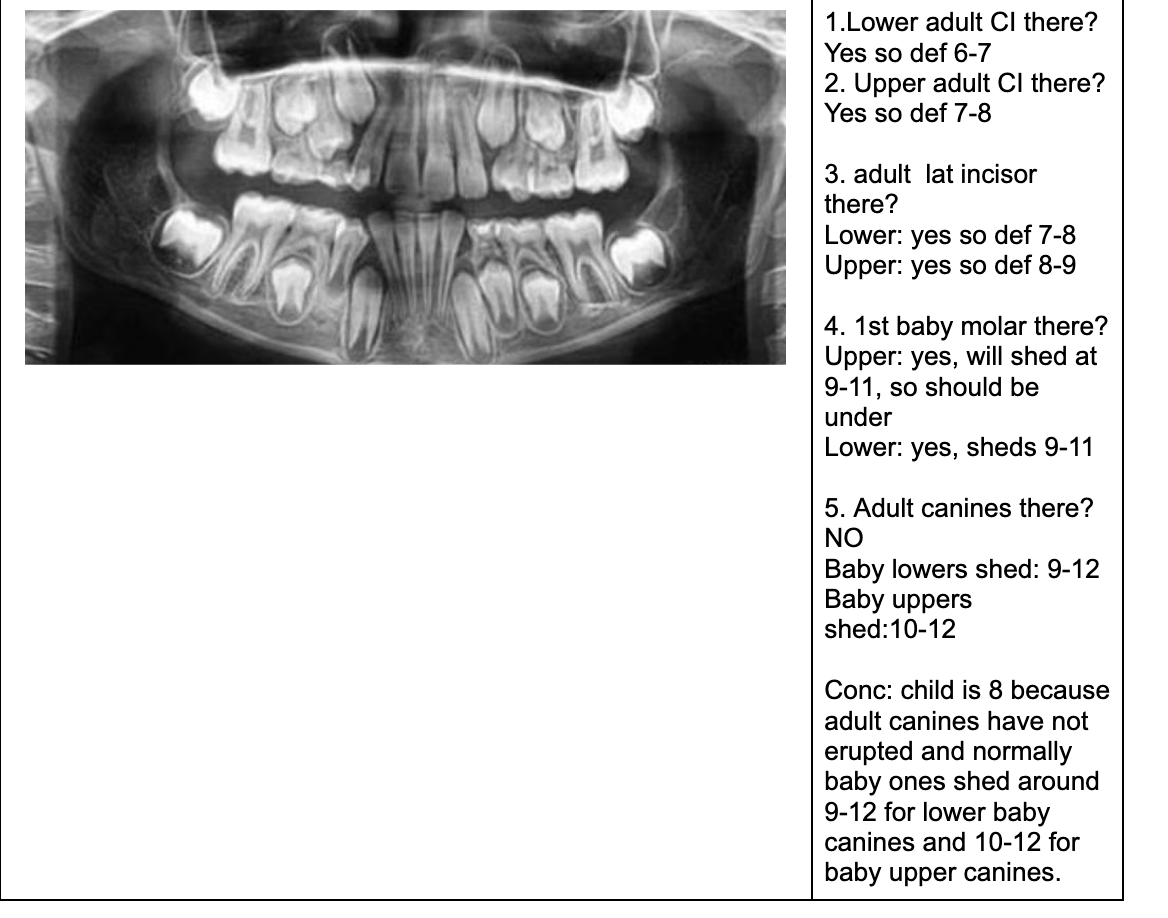

1.lower adult CI there? YES, so def 6-7

1. Upper Ad. Ci there? NO, so either 6-7 or under

Last molar crown not really formed so 6?

NOTE- THE 8’s - crown starts developing at 9 yo.

1.Lower adult CI there? YES. so def 6-7

1. Upper adult CI there (they normally erupt 7-8)? NO, baby ones should shed at 6-7.

Conc: pt. Is 6 y.o